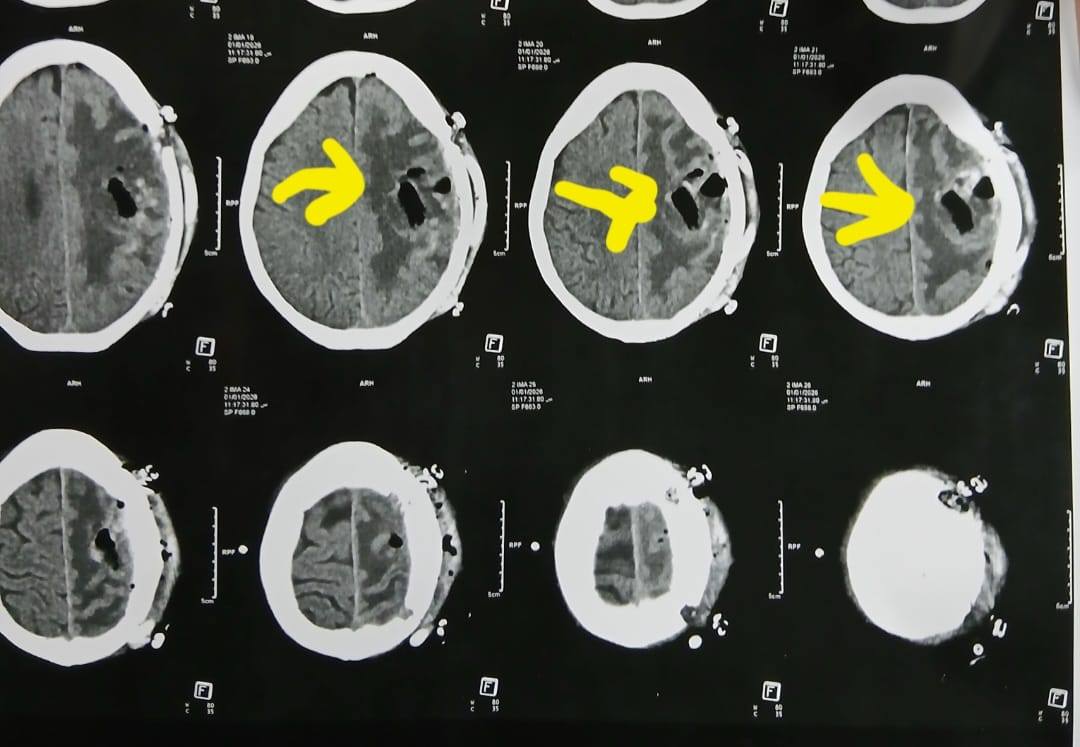

وكشف الدكتور إبراهيم الغريب رئيس قسم جراحة المخ والأعصاب بالمستشفى، أنه تعود تفاصيل الحالة إلى استقبال المستشفى المريضة بالعيادة الخارجية وهي تشكو من تنميل وضعف بالجانب الأيمن وثقل بسيط في الكلام، وبإجراء الفحوصات اللازمة من أشعة مقطعية ورنين مغناطيسي بالصبغة، تبين وجود ورم بالمخ، وتم إعطاؤها العلاج المناسب لحين استكمال الفحوصات.

وتابع "الغريب"، أنه مع تدهور حالتها الصحية، جرى التعامل مع الحالة بشكل عاجل، حيث تم تجهيز المريضة للجراحة، وحجز سرير بالعناية المركزة، وعمل عروض لكافة التخصصات، مع توفير الدم والبلازما واستكمال جميع التحاليل والفحوصات اللازمة، ودخلت المريضة غرفة العمليات، حيث أجريت جراحة مخ دقيقة شملت فتح عظام الجمجمة، وفصل الورم تدريجيا عن أنسجة المخ مع السيطرة على الأوعية الدموية المغذية له.

أشعة المريضة

الأشعة الخاصة بالمريضة

الأشعة